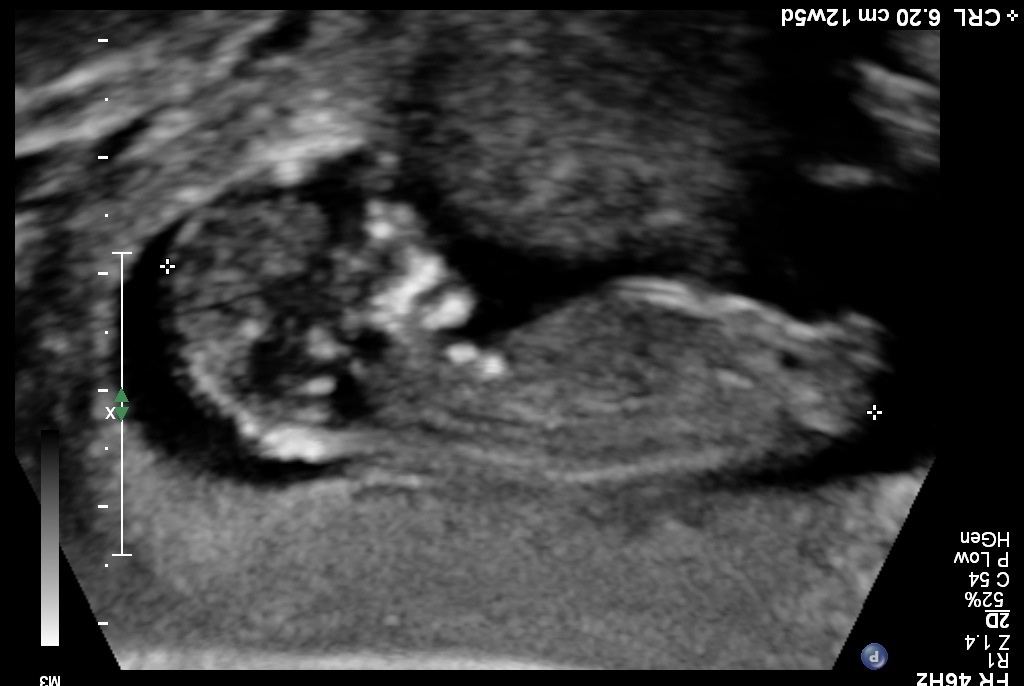

I know it is early and this isn't a great pic, but any thoughts on gender? I was 12 weeks, 1 day.

Yeah I wasn't given any good profile shots.:-/ Here's what I have...Attachment 12408Attachment 12409Attachment 12410

Sure let me try...Attachment 12423Attachment 12424Attachment 12425Attachment 12426